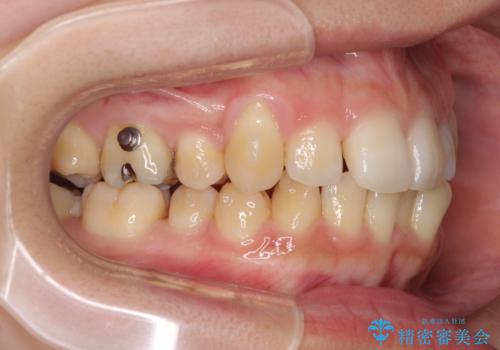

八重歯の抜歯矯正 補助装置を用いたインビザライン矯正

八重歯の移動量が多く、インビザライン単体での治療は困難と判断し、補助装置により八重歯移動後にインビザラインを用いることとしました。

装着時間をしっかりと守ってくださったので、予定通りの期間で終了することができました。